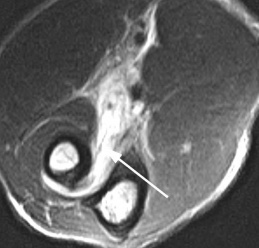

(Справа) На осевой КТ виден перелом медиального края локтевою отростка без смещения. Продольные переломы проксимальною конца локтевой кости без смещения иногда очень сложно обнаружить на рентгенограммах. (Слева) На фронтальной МРТ Т1ВИ у этою же пациента видна линия неполною перелома с низким сигналом в локтевом отростке.

(Справа) На осевой MPT PDBИ FS у этого же пациента определяется перелом, окруженный отеком костного мозга с высоким сигналом. Повреждение этой области локтевого отростка у спортсменов-метателей, применяющих верхний бросок, не является редкостью и поэтому ею следует учитывать при дифференциальной диагностике боли в локтевом суставе у этих пациентов.